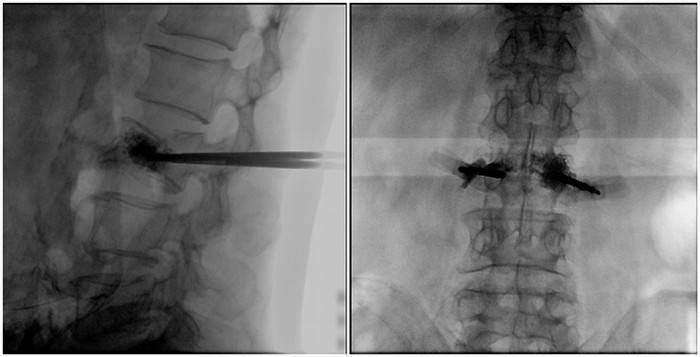

(2)術(shù)中切口5毫米,借助大視野平板C臂機PLX119C的高清圖像,確定進針的方向及進針的深度。經(jīng)椎弓根向椎體置管,建立通道,插入骨擴張器(球囊)。球囊擴張恢復(fù)椎體高度,并在椎體內(nèi)形成空腔,確定骨水泥的注入劑量,并注入骨水泥觀察其擴散情況。

大平板C臂機的高清圖像

(3)注射過程需要C臂透視來查看骨水泥的分布情況,預(yù)防骨水泥外露進入椎管內(nèi)引起神經(jīng)損傷。椎骨體內(nèi)骨水泥填充完好以后,拔出工作套筒按壓止血,并繼續(xù)俯臥位十分鐘,等待骨水泥硬化,最終手術(shù)圓滿完成。